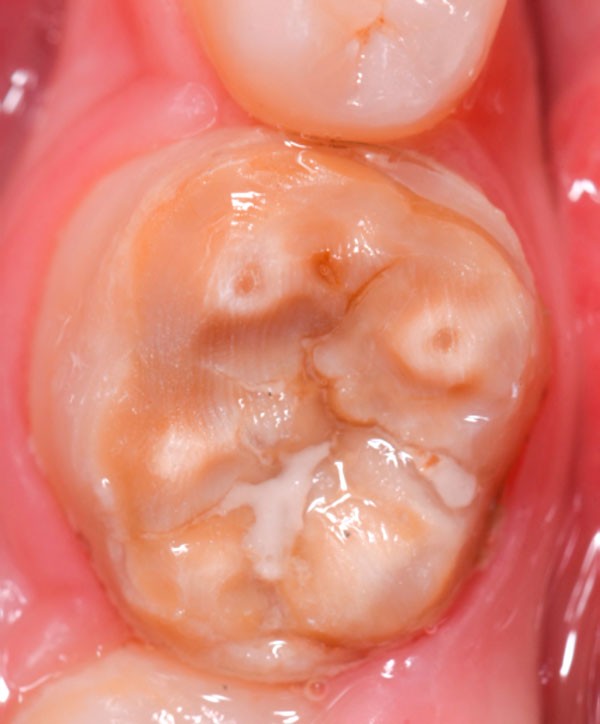

Au moment de la séquence préparation/empreinte, il faut faire un scellement dentinaire immédiat (IDS) décrit par Pascal Magne [5]. La tendance la plus récente est d’appliquer l’adhésif habituel du praticien puis de le recouvrir d’une fine couche de composite fluide [6, 7]. De cette façon, le praticien peut s’affranchir de l’utilisation d’un MR3, comme dans les premières publications de Pascal, et conserve les nombreux avantages de la procédure. La qualité de l’adhérence, le masquage des colorations et la simplification des contours que l’IDS permet sont 3 atouts incontournables pour les restaurations indirectes (fig. 1 à 3).